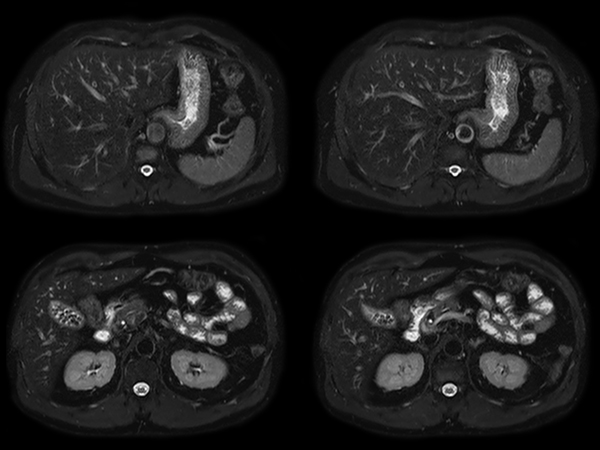

Total Torso imaging - MultiVane XD